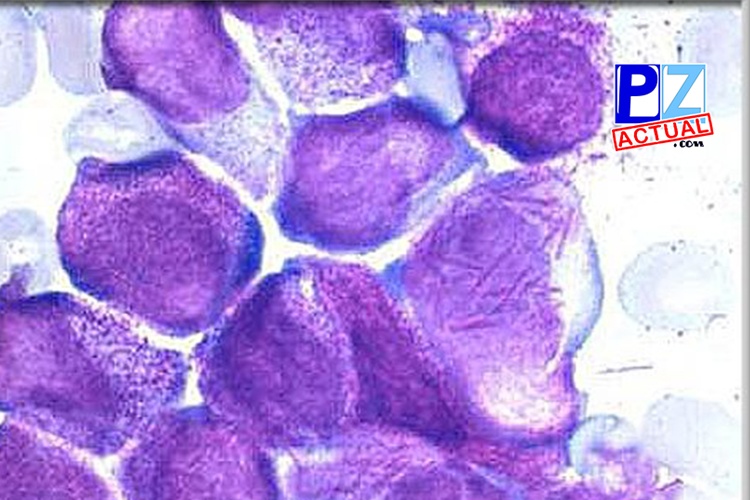

Especialistas del Hospital México logran nueva fórmula para el tratamiento de la leucemia promielocítica.

Este son el tipo de cosas que hacen diferente a nuestro sistema de salud, profesionales que impactan en la vida…